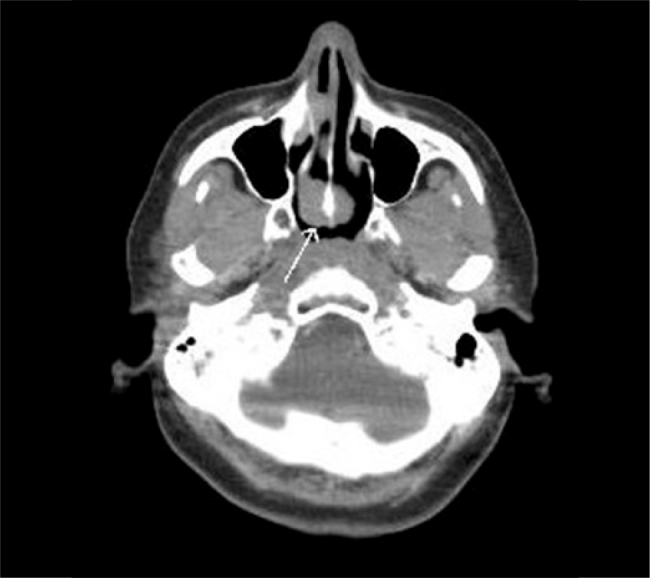

Case report: A 33-year-old woman presented with cervical swelling that had persisted for one month. Ultrasound examination and biopsy confirmed the diagnosis of RDD. The patient subsequently developed raccoon eyes and bilateral eyelid oedema. Laboratory investigations revealed bicytopenia and leukocytosis. Unexpectedly, bone marrow aspirate and flow cytometry confirmed the presence of acute myeloid leukaemia (AML). Following repeated complaints of headache, brain magnetic resonance imaging revealed a callosal lesion, suggestive of a space-occupying lesion. One year later, the patient relapsed and died from septicaemia.